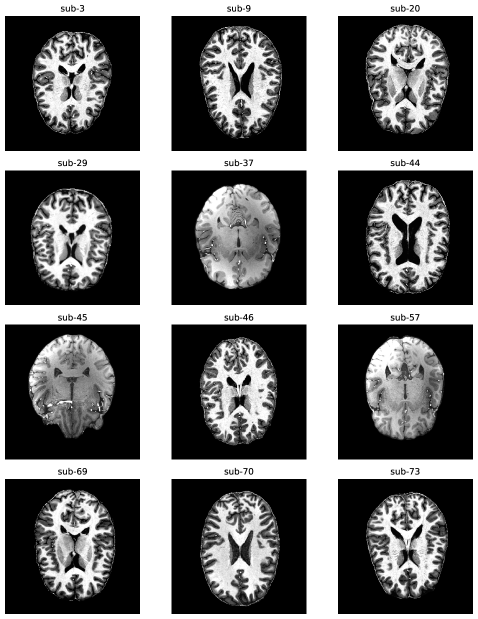

The LUMIR challenge uses SLANT to obtain labelmaps for the Ultracortex dataset, and downsamples the images to 1mm isotropic. However, this preprocessing has two undesirable effects. First, submillimeter resolution images can provide additional cytoarchitectural detail and act as a bridge between low resolution in-vivo scans and high resolution histology images. Lowering the resolution can lead to loss of this information and defeats the purpose of using high-resolution scans in the first place. Moreover, this is not representative of clinical and research workflows where high-resolution blockface scans are used as an intermediate modality between in-vivo scans and histology slides (nextbrain; alegro2016multimodal). Second, the MP2RAGE sequences in the dataset are both qualitatively and quantitatively different compared to the MP-RAGE sequences seen in the OASIS dataset. This constitutes a significant source of domain shift that leads to poor performance of SLANT on the Ultracortex dataset, making it unsuitable for robust evaluation. This aspect is not discussed and possibly unaccounted for in the original evaluation. We examine the volumes and histograms of the subjects and show that the MP-RAGE sequences (corresponding to subjects sub-37, sub-45, sub-57) indeed look qualitatively different than the MP2RAGE sequences in Figure 5. Specifically, histograms of the MP2RAGE sequences are characterized by two or three peaks, close to the extreme values of the intensity range, while the MP-RAGE sequences have a more unimodal distribution with a single dominant peak.